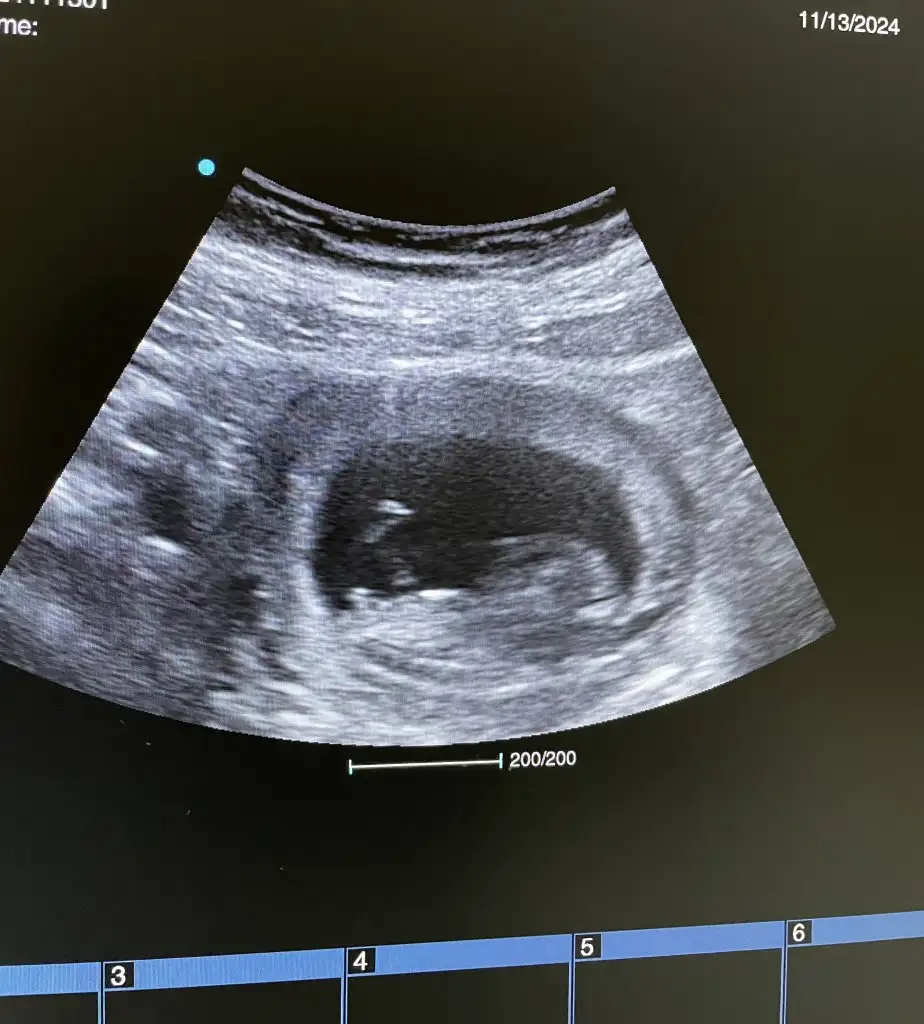

6 haftalık gebelik keseden cinsiyet tahmini yapabilen varmı

• 3d589de3-ee0e-4ab8-a94e-5d9b4bfeb109.webp

3d589de3-ee0e-4ab8-a94e-5d9b4bfeb109.webp

18 KB · Görüntüleme: 56

Öncelikle hayırlı olsun. Nub için çok küçük . Ramzi teorisi içinse kız olabilir. Çok bildiğim bir şey değil 😊 hayırlısı olsun